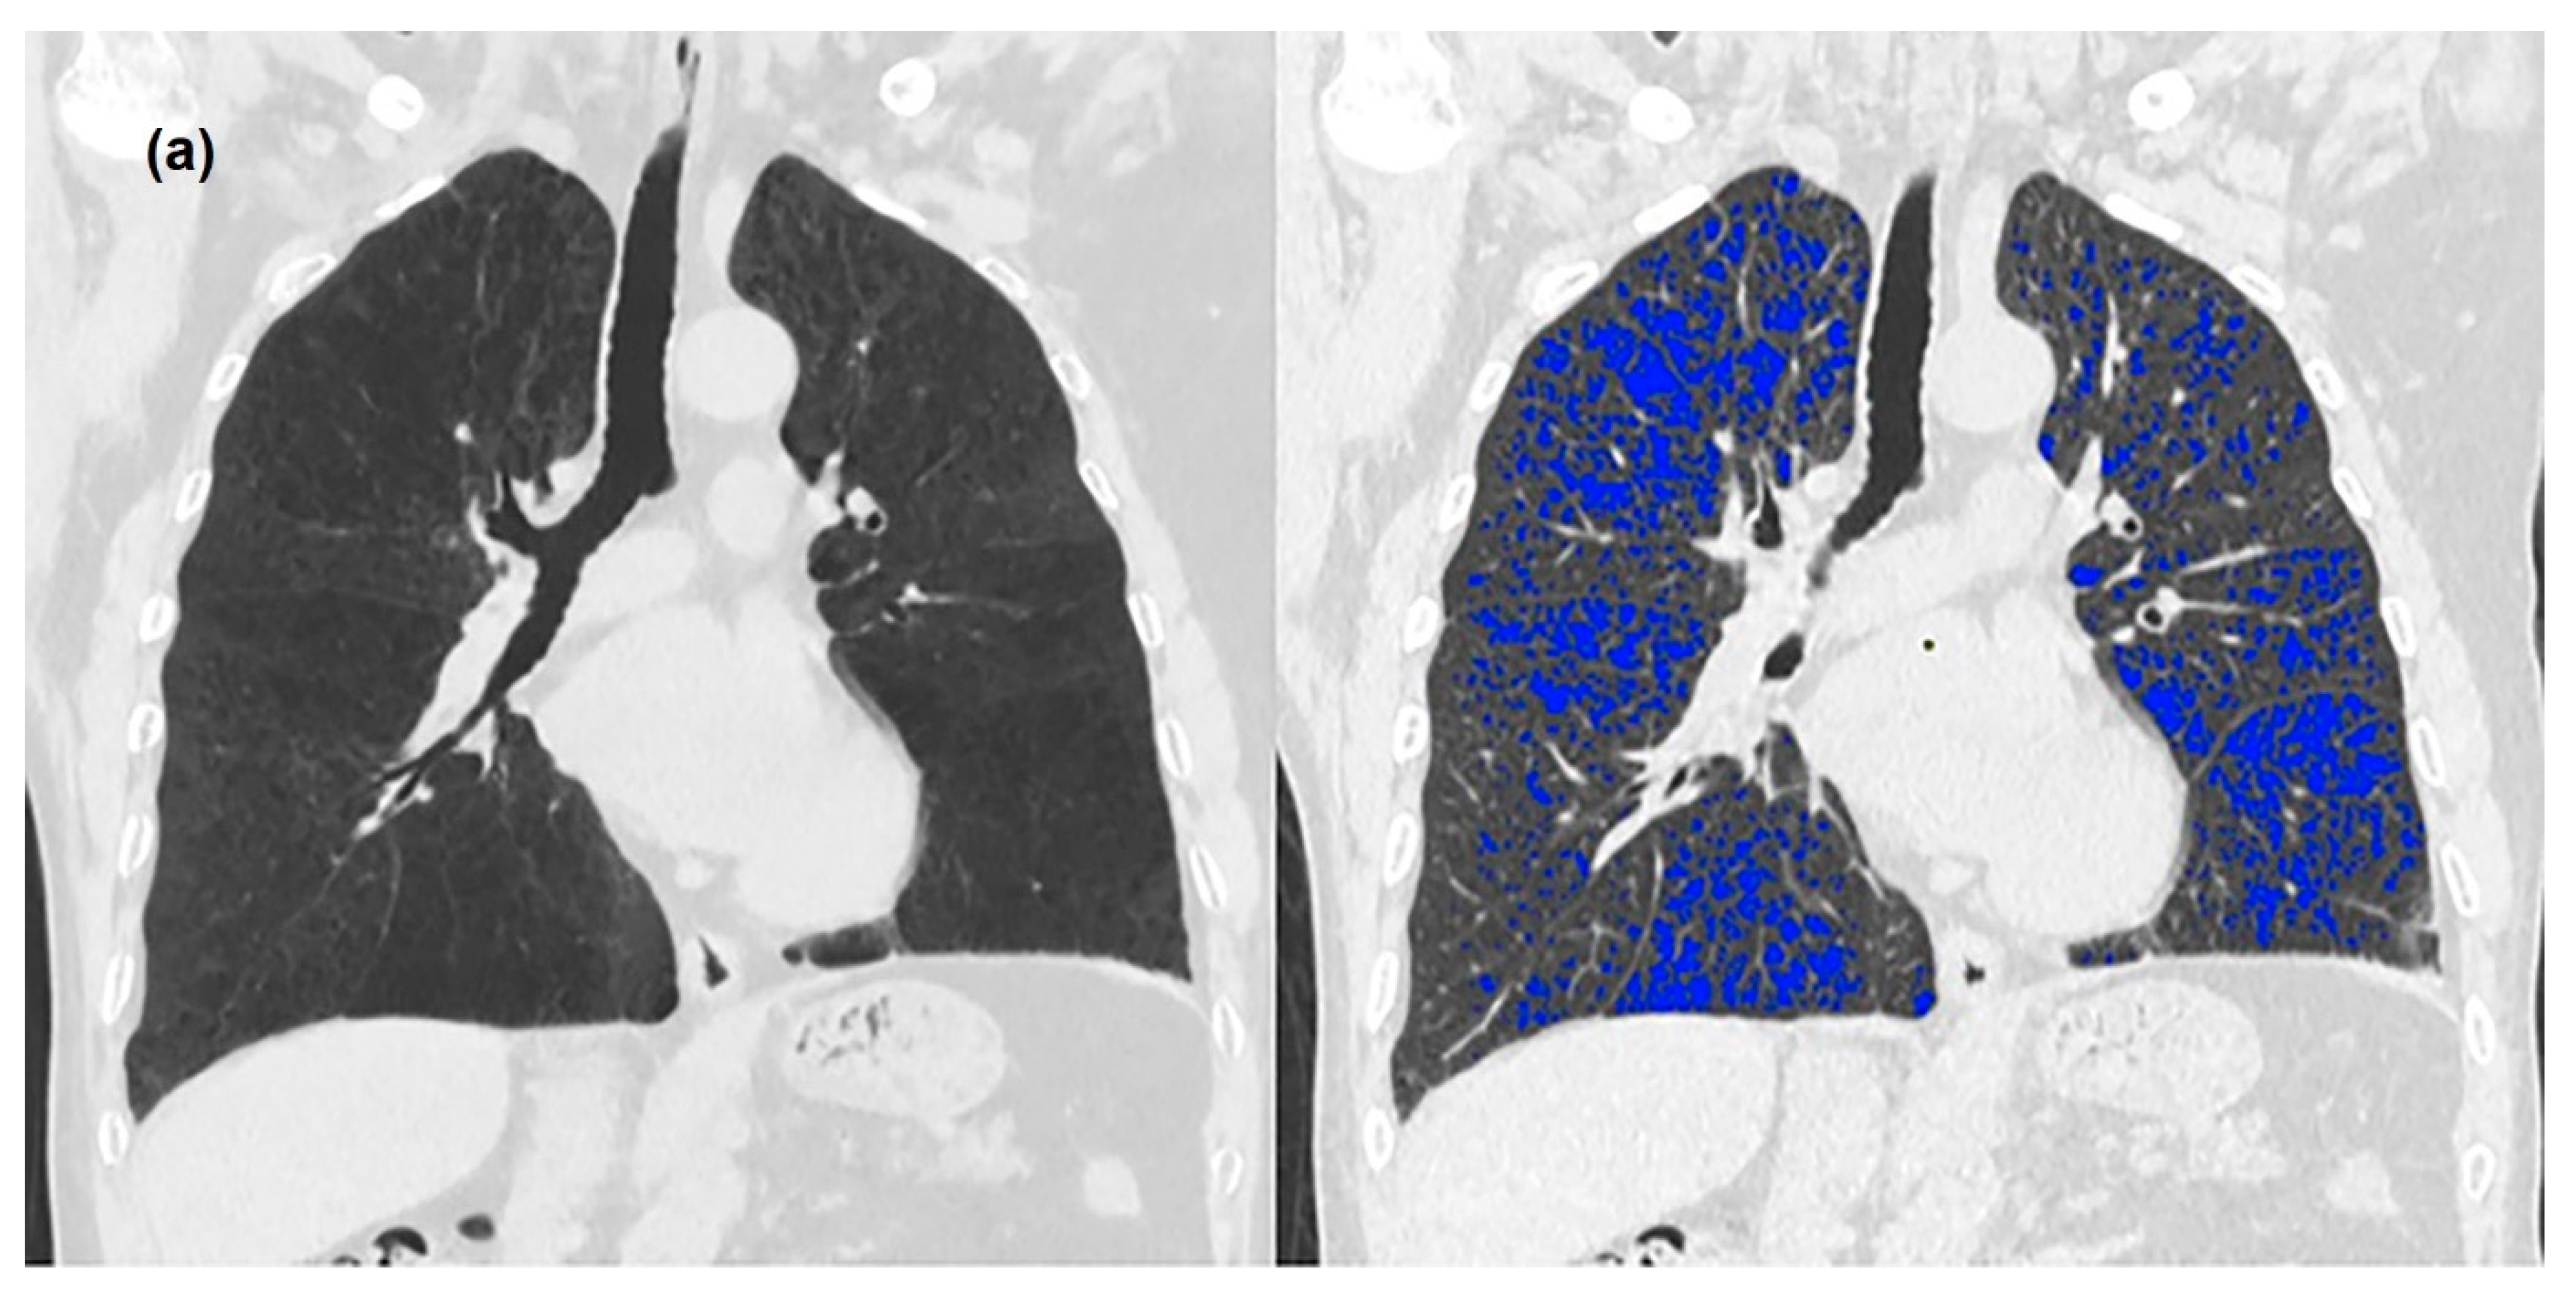

3. Results

3.2. Quantitative Measurements of Standard-Dose and Ultra-Low-Dose CT

4. Discussion